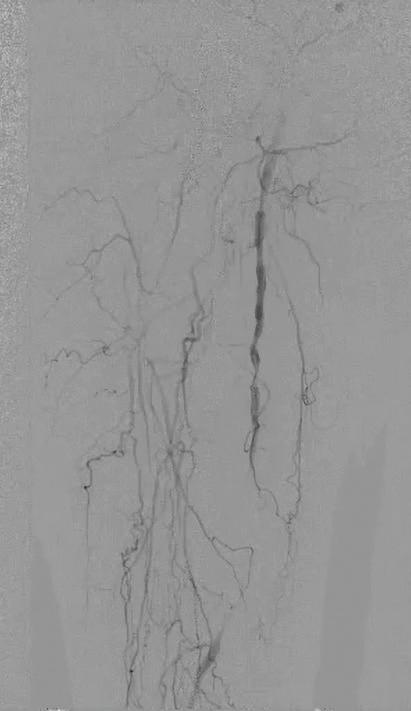

THESE REMAIN EARLY DAYS for transcatheter arterialization of the deep veins (TADV) in the setting of patients with severe chronic limb-threatening ischemia (CLTI), says Daniel Clair, MD, one of the principal investigators in key clinical trials of the procedure, but the learning-curve process promises that “we are going to continue to see slow but not insignificant improvement in results” with the technique.

Late last year, Clair presented two-year outcomes from the prospective, multicenter, singlearm PROMISE II trial of the LimFlow system (Inari Medical) for TADV in so-called no-option CLTI patients at the 2024 edition of Vascular Interventional Advances (VIVA) in Las Vegas (Nov. 3–6), demonstrating sustained limb salvage and wound healing.

All patients enrolled in the trial had Rutherford class 5/6 disease, with a total of 105 CLTI patients undergoing the procedure between 2018 and 2022. At VIVA, Clair reported a limb salvage rate of 65% and improvement in Rutherford classification: 65.8% of patients had class 4 or below and 54.3% had class 0. Wounds were completely healed/healing in 82% of patients and the mean pain score was 1.2 out of 10. When combined with the PROMISE I trial, the two-year limb salvage rate was 68%, with no differences observed based on age, sex, race, baseline Rutherford classification, diabetes or dialysis, Clair had added.

Those type of data are likely to be built upon, with the future portending wider use of TADV, Clair reflects in a recent interview with Vascular Specialist

“What is likely is that you are going to see an expansion in the use of this technology in patients who perhaps are not as far down the path of ischemia as we have seen,” he explains. “I also think that there will likely be some complementary role in terms of arterial revascularization in people who have very bad distal disease.”

The data show that 25–30% continue to lose their limbs even when TADV is used, so opportunities to enhance benefits from the procedure require exploration, Clair continues. “The use of deep vein arterialization with

vascular growth factors to enhance angiogenesis in the foot might be ideal. Right now, we are trying to understand how to optimize the venous flow in the foot to enhance, expedite and speed up the arterialization and delivery of oxygen to the tissues in the foot so we don’t lose the forefoot or toes, but we get them this delivery of oxygenated blood so they can heal the wounds that they have. Part of what we’re doing is trying to look at the angiographic and duplex data from PROMISE I and II patients to see if we can identify who are the patients who did really well and the patients who did not do well, and can we identify differences between them.”

Clair is clear on this direction of travel. The patient population who informed the clinical trials typify the necessity of the procedure, he says. “In the past, essentially everyone I have enrolled in these trials is a patient who likely would have had an amputation, and I can say that because I have watched them worsen before enrolling them, having tried other measures to help get them through. In the PROMISE trials, we carried this out in what I call the sickest of this group of patients, because they had to be externally validated as having no option; they had to be more than a month out from any previous angiogram or attempted intervention; and they had to have a wound on their foot in order to allow them to qualify. One of the critical issues now is, while that was what the trial was, in the community this technology is being used more in patients who don’t have good options, but who get an angiogram, can’t have percutaneous intervention, and the next day they are going for this venous arterialization.”

believers in the technology start to embrace it and make referrals. His previous involvement in angiogenesis trials underscore how sick the PROMISE patients are, he says: in those, patients who had rest pain, severe claudication, and no foot wound could be enrolled. “[PROMISE trial participants] are patients who have not been studied in any previous trial because, frankly, they are sicker than any company was willing to look at, particularly in interventional trials.”

Some form of forefoot amputation is not unusual in the first two to three months after TADV, nor is an increase in pain in the first month, PROMISE data reveal.

“It’s unusual for these patients to keep everything because they have such severe disease in the foot by the time they present for treatment with this therapy,” Clair points out.

“Intriguingly, in PROMISE I, with every patient who kept their limb, if they made it three months with their limb on, they were going to keep their limb for the long term. In PROMISE II, there were very few patients who lost their limb beyond that first three-to-four-month period. If you get a good venous arterialization, and you see a response through six to 10 weeks, these people are likely going to keep their limb.”

Meanwhile, PROMISE III will take another extended look at the same group of patients “in a little more real-world applications,” Clair adds. “So many of these patients have bilateral limb ischemia, so we included patients in whom you could do the procedure on both sides. We did not mandate an independent review committee; we did not mandate a 30-day waiting period between a previous angiogram or attempted intervention and moving on to venous arterialization.”